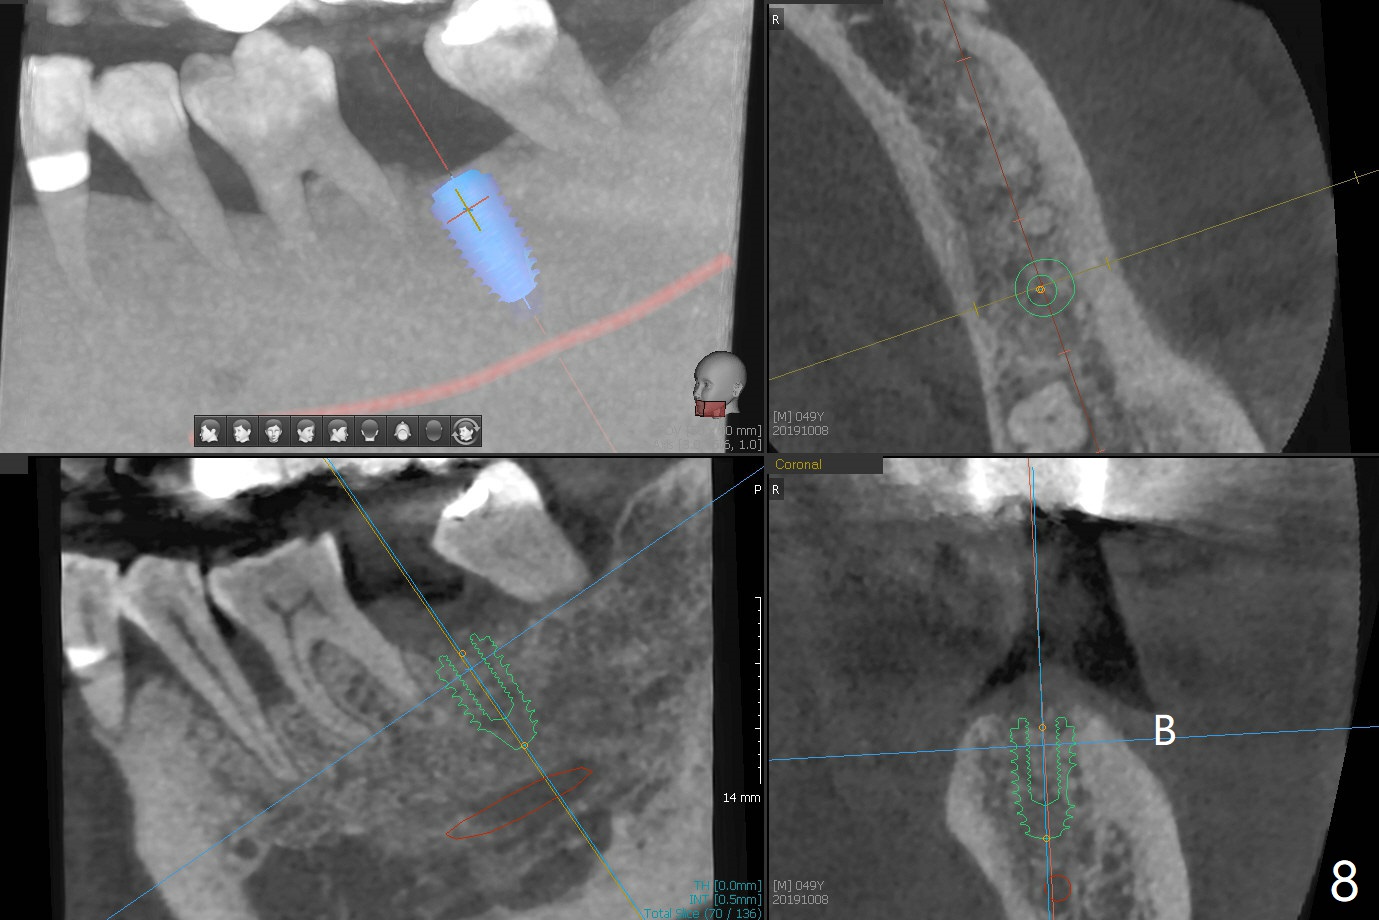

A 49-year-old man returns for #14 and 15 implant impression. The tooth #18 is buccally shifted with mobility, which is incompatible with #14 and 15 restoration. The tooth has to be extracted with socket preservation (Fig.1). A piece of 6-month collagen membrane is used to cover allograft. The socket is healing 9 days postop (Fig.2), probably related to its small wound. Three months and a half postop (Fig.3), CT shows bone healing (Fig.4 sagittal (thin) section, 5 (thick section); 6 (coronal (thin) section). A 5x8.5 mm implant will be placed (Fig.7,8).